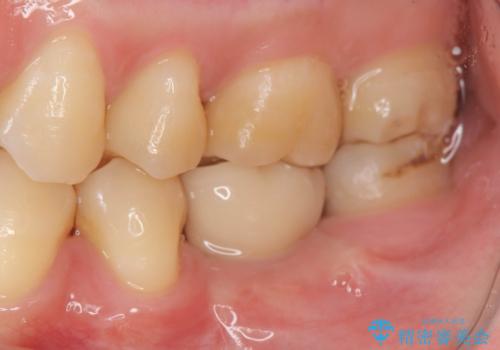

大臼歯の欠損 インプラント治療

- 44万円(インプラント・アバットメント・ジルコニアクラウン・仮歯)費用は治療当時の料金となります

ブリッジのように前後の歯を削ることなくしっかりと咬合機能の回復を行うことができました。